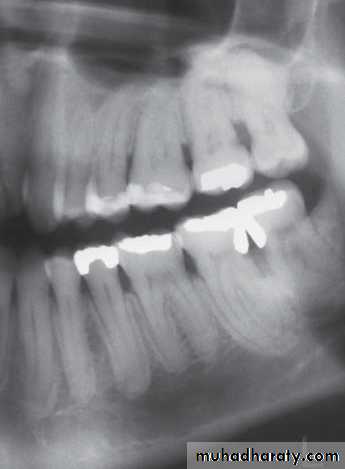

• Presence of sequestra . • Increase in bone sclerosis. • Widening of PDL space • Thicknening of lamina dura.

(BRONJ). Exposed necrotic bone is seen at the lingual side of the mandibular right second molar. A lesion with osteolysis and osteosclerosis extends from second molar to first premolar region

( A and B ) of the same patient taken 7 years apart reveal thickening of the lamina dura around the teeth.

A

B

( A and B ) of the same patient taken 1 year apart demonstrate a developing sclerotic bone pattern with a sequestra (arrow) related to bisphosphonate therapy.